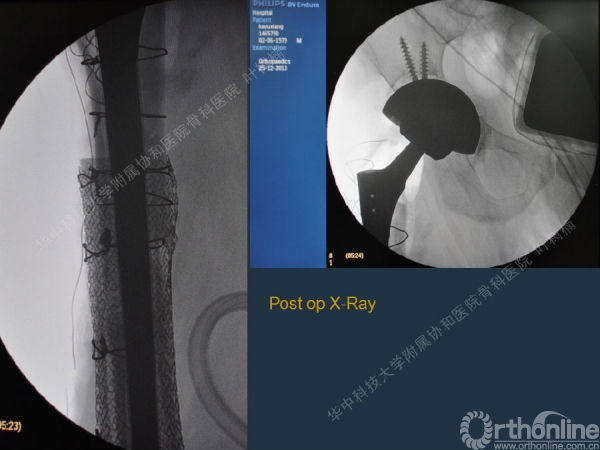

股骨侧翻修